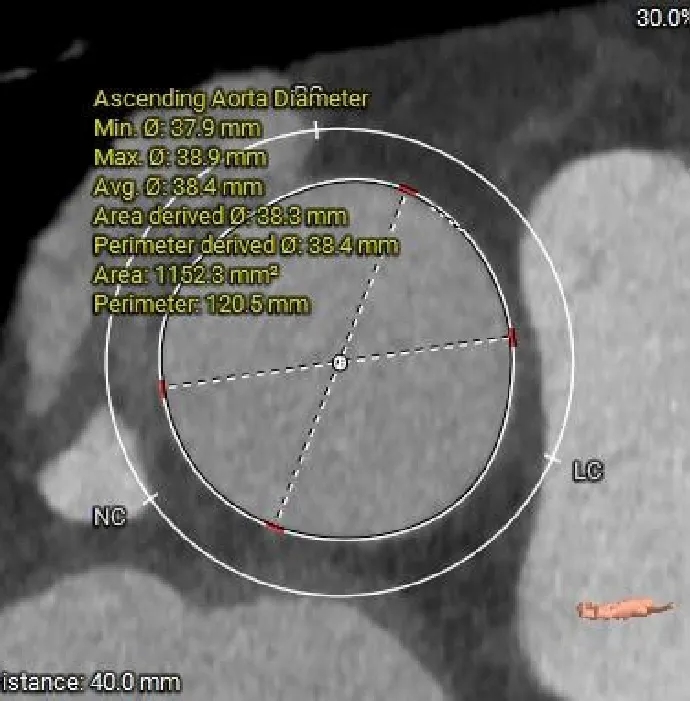

AAO

38.4mm

术前CT分析

主动脉根部测量

38.8mm